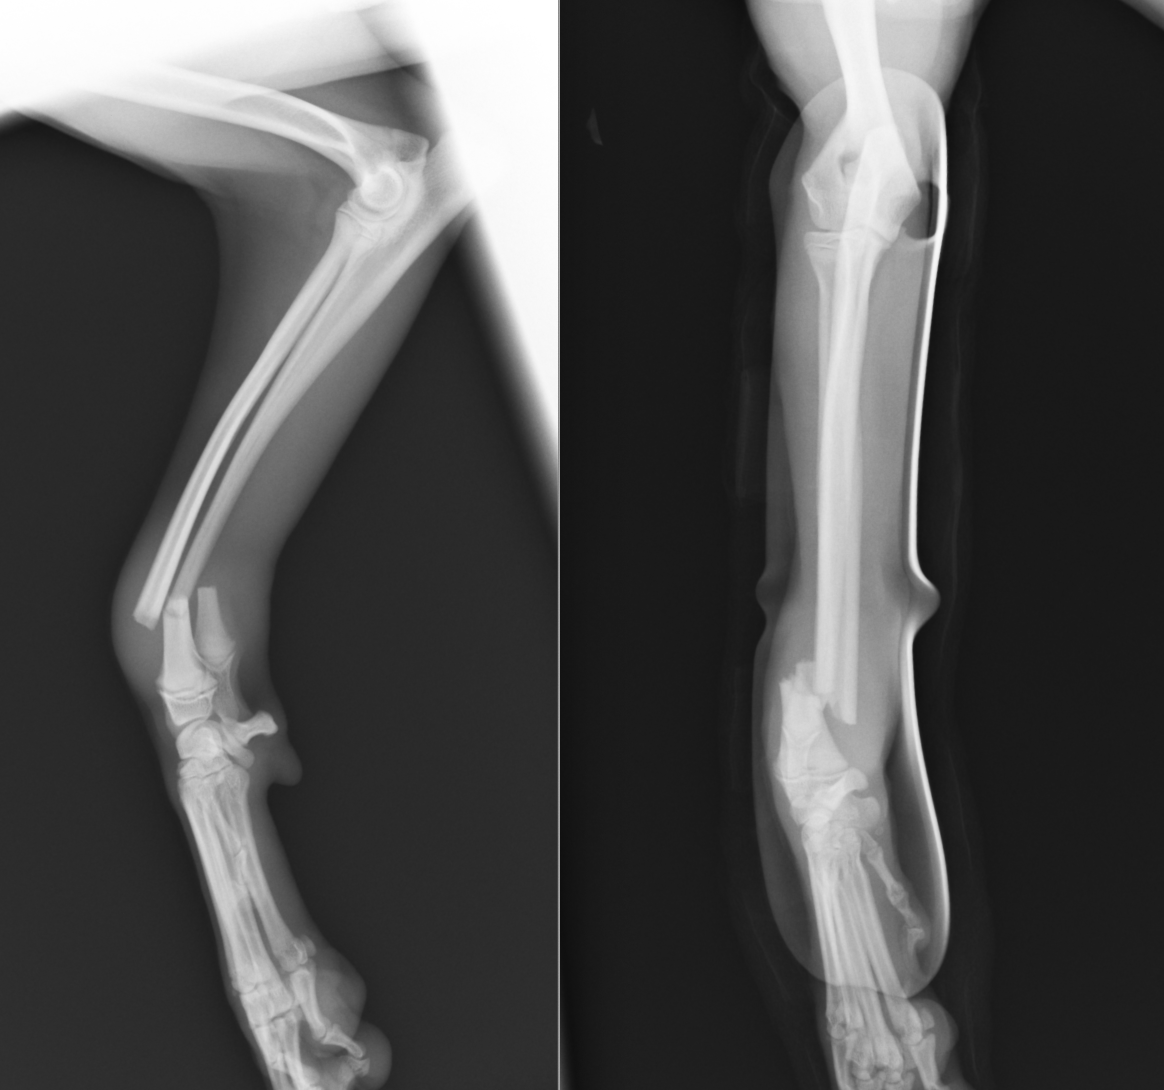

少し位置が異なる別の骨折の子のレントゲン画像です。骨の中央付近の骨折なので診断名は橈尺骨骨幹部短斜骨折となります。こちらも直ぐに手術を行いました。

橈骨遠位骨幹端での骨折が確認できました。

完全に折れてしまっている状態です。